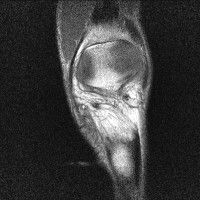

무릎 mri 간단히 봐주실 수 있으시나요 ㅠㅠ

안녕하세요 8년전 십자인대 수술하고 최근 무리한 운동에 무릎 불편감이 생겨서

mri 찍었습니다.

진단결과는 첫 찍은 병원에서 활액막염 이라는 진단을 받았습니다. 혹시 봐주실 수 있으실까요?

올라온 MRI가 단편적이라서 정확한 진단에 어려움이 있지만 십자인대에는 큰 이상이 있지는 않은것 같으며, 무릎관절내 물이 있는 것으로 보아 활액막염의 진단이 맞을 것 같습니다.

하지만 단편적인 영상이기 때문에 촬영병원에서 정확한 판독지 등을 받으시는 것이 좋겠습니다.